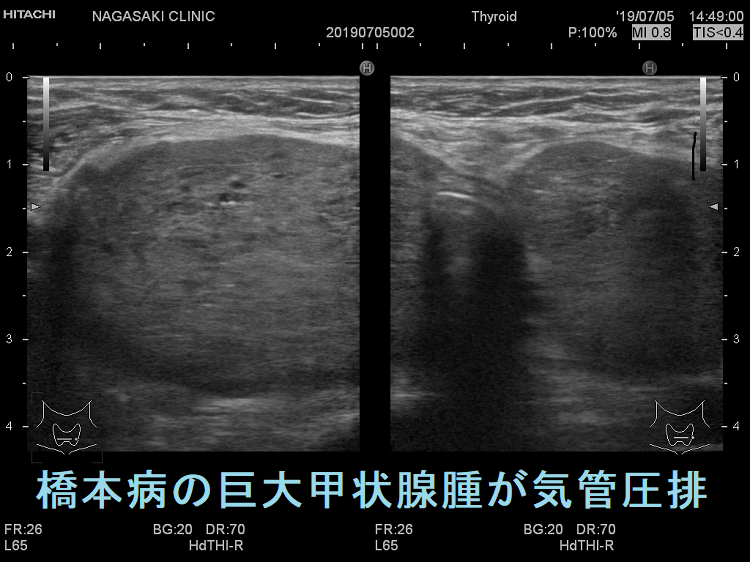

ケース① 橋本病巨大甲状腺腫(気管圧排)

ケース③ 橋本病の巨大甲状腺腫が気管圧排